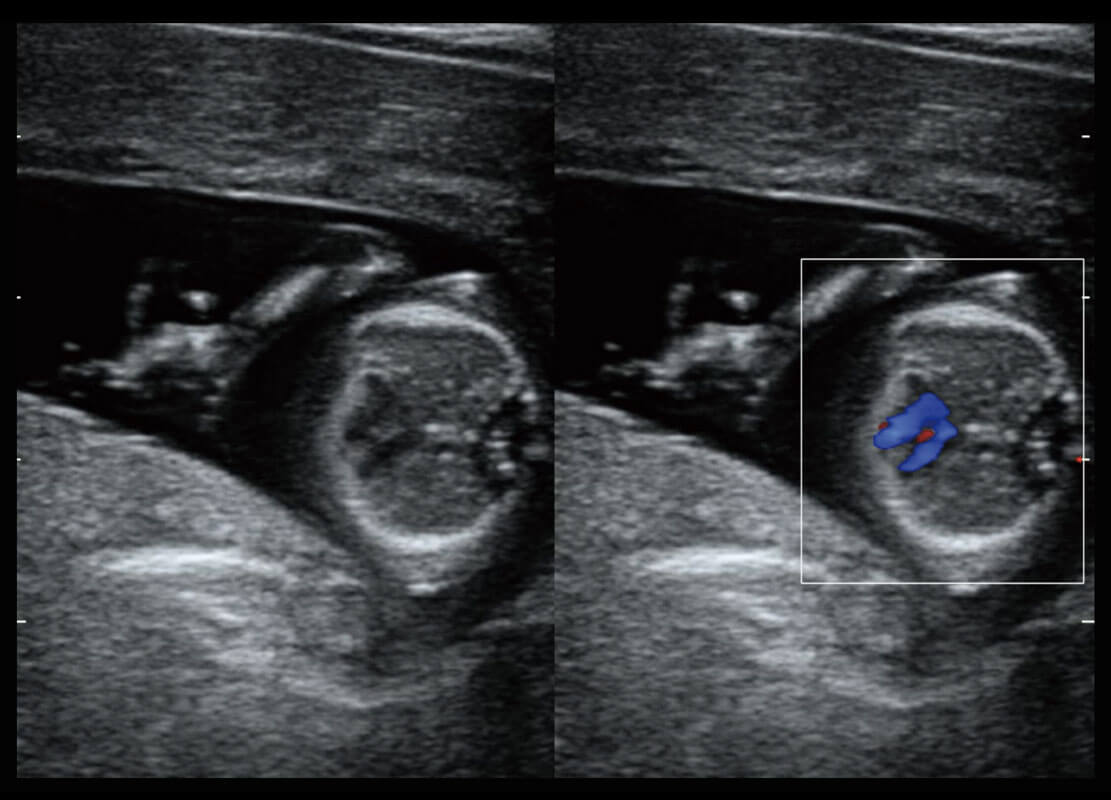

乳腺超声 / 新生儿

P60搭载宽频带线阵探头、宽景成像、弹性成像技术,为您提供乳腺应用方案。P60支持高频相控阵探头、线阵探头、腹部高频探头、腹部微凸探头等,丰富的探头群搭载敏感的彩色血流成像,适用于新生儿多种脏器检测要求,满足新生儿筛查需求。

• 新生儿肝血管癌

• 新生儿脊髓圆锥

• 新生儿心脏